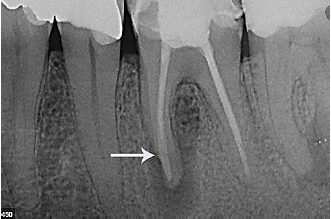

Observe a imagem a seguir:

A seta aponta lesão radicular, na imagem, acima, em qual dente?